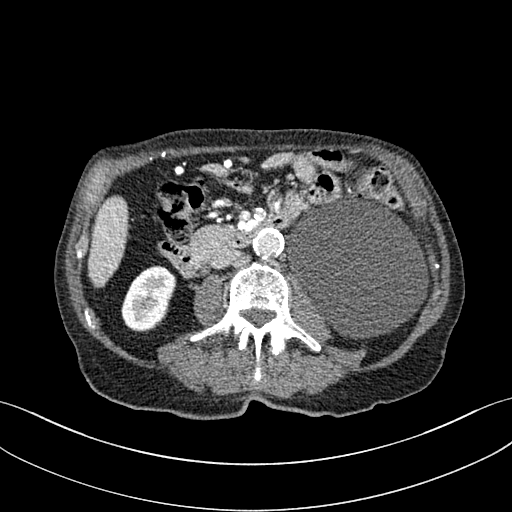

As shown in Table 3, DIP has exhibited the worst performance among all the methods. On the other hand, the ConsensusNet yielded a better FID and TML than BM3D but a lower PSNR and SSIM than other methods. The ConsensusNet divided the original projection data of the low dose CT image into two subgroups and back-projected to create the noisy input signal. Consequently, the noisy input image is much noisier than the original LDCT image. Also, the structural loss occurred during the generation of noisy images, so as a result, the PSNR and SSIM of this method are lower than other methods. Texture matching loss (TML) is used to measure the texture difference between the reconstructed and original images. The lower value of TML indicates that the generated texture is similar to the original. In comparison, FID estimates the distance between the distribution of the generated image and real images. A lower value of FID signifies the generated images are more similar to the original image. The current deep learning era demands a denoised image with a low value of these metrics. These denoised images may be used as input for other image classification tasks or segmentation networks. In this regard, the ConsensusNet is superior to the BM3D because it uses the deep neural network’s expression power. CycleGAN is another powerful unsupervised method for image-to-image translation; it achieved better performance than the other methods. However, CycleGAN has a lot of bottlenecks, e.g., longer training time, computation power, hyper-parameter tuning, etc. All these bottlenecks make CycleGAN ill-suited for practical deployment. Meanwhile, our proposed method has achieved the highest PSNR, SSIM, FID, and VIF among all the other methods. Next, we compare the result of denoising visually in Figure 6. It can be observed that the proposed method performs significantly better than the other unsupervised methods. BM3D output produced a blurry denoised image and contained many splotchy artifacts. The same blurriness can be observed in the output of ConsensusNet, and DIP, although noise suppression is adequate, and splotchy artifact is absent. In the output of CycleGAN, we can observe the presence of residual noise, especially in the high noise regions. Next, we identified one low attenuated lesion in the sample image and marked the lesion with a red colour bounding box. The zoomed view of the region inside the bounding box is given in Figure 7. In our method’s output image, the lesion’s visibility is enhanced significantly than in other methods. Despite being an unsupervised method, the visibility of the lesion is comparable with the original NDCT image. Also, from the zoomed view, we can perceive that our method has suppressed the granular pattern without losing the original image’s texture.

Refer to caption

(a) LDCT

(b) BM3D

(c) DIP

(d) CycleGAN

(e) ConsensusNet

(f) Proposed

(g) NDCT

Figure 6: Result of denoising for comparison. We have shown an example of denoising performance on image taken from the 2016 NIH-AAPM-Mayo Clinic Grand Challenge dataset. The display window is [140140-140, 260] HU for better visualization of low attenuated lesion. Readers are requested to zoom in for better view.